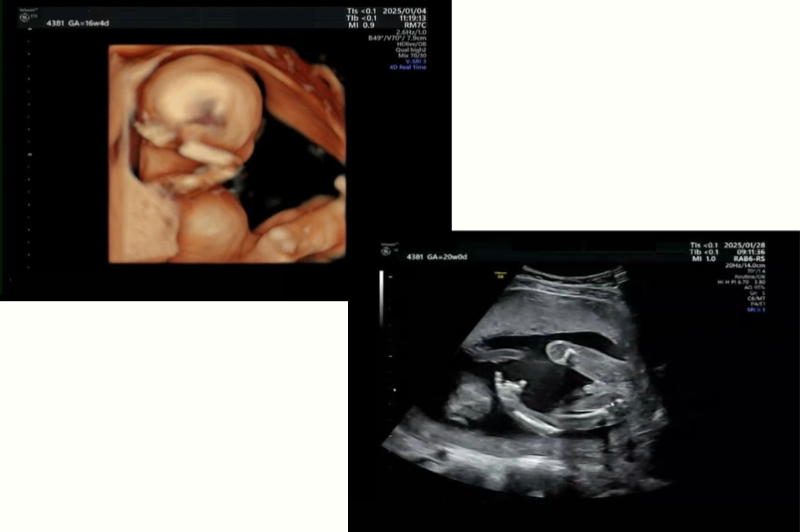

ゆんさん胎児エコー

「(左)“頭に手をまわしてくつろいでる”妊娠16週のベビJと、(右)“指しゃぶりをしている”妊娠20週のベビJです。マイペースな赤ちゃんみたい♪」